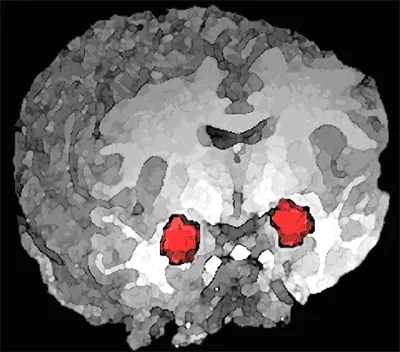

Now here’s where things get really interesting. While some parts of your brain grow with mindfulness practice, others actually shrink. Specifically, your amygdala, that almond-shaped cluster of neurons that acts as your brain’s alarm system. Participant-reported reductions in stress were correlated with decreased gray matter density in the amygdala, which is known to play an important role in anxiety and stress.

Let’s be clear about what this means. Your amygdala doesn’t disappear or stop working. Instead, it becomes less reactive, less likely to trigger unnecessary stress responses. Mindfulness has a unique ability to down-regulate the amygdala, the brain’s fight-or-flight center, leading to reduced emotional reactivity and a steadier mood baseline. The fascinating part? Not only does the amygdala shrink after mindfulness practice, but the functional connections between the amygdala and the pre-frontal cortex are strengthened. This means your thinking brain gets better at regulating your emotional brain.

The connection between the amygdala and the rest of the brain gets weaker, while the connections between areas associated with attention and concentration get stronger, allowing you to recruit higher-order prefrontal cortex regions to down-regulate lower-order brain activity. Essentially, mindfulness training helps your rational brain better manage your emotional brain. Mindfulness meditation training decreased amygdala-sgACC functional coupling relative to a well-matched comparison relaxation treatment without a mindfulness component, providing a specific neural pathway for stress reduction.